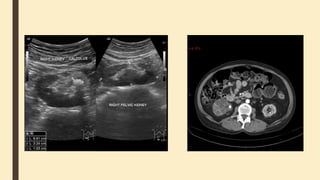

Renal dystopia

also known as renal ectopia, is

a congenital renal anomaly

characterized by the abnormal

location of one or both of

the kidneys.

They can occur in several forms:

■ cross fused renal ectopia

■ ectopic thoracic kidney

■ pelvic kidney

Renal dystopia also knownas renal ectopia, is a congenital renal anomaly characterized by the abnormal location of one or both of the kidneys. They can occur in several forms: ■ cross fused renal ectopia ■ ectopic thoracic kidney ■ pelvic kidney